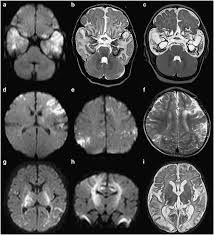

In children older than 3 months and in adults brain biopsy: Herpesviral encephalitis, or herpes simplex encephalitis (hse), is encephalitis due to herpes simplex virus. • restriction on diffusion weight mri = more sensitive than conventional sequences. Misra uk, hashmi aa, kalita j. Diagnostic uncertainty and empirical management in pcr negative encephalitis. It is a severe condition brain mri may show limbic encephalitis (55) or diffuse t2 and dwi hyperintensities in the white matter, associated with restricted diffusion (54). Herpes simplex encephalitis occurs as 2 distinct entities: Mri is the imaging of choice in suspected cases of viral encephalitis, although ct scanning may be used where mri facilities are not available. The patient had initially improved after medical treatment. Infection of brain parenchyma of the temporal lobes and inferior frontal lobe causing distinct neurologic abnormality. Dhawan a, kecskes z, jyoti r, kent al. Associated with hsv encephalitis (strong evidence). In addition, because of the involvement of the.

The laboratory diagnosis of autoimmune encephalitis. The study analysed serially acquired magnetic resonance images (mri), of patients with acute hsv encephalitis who had neuroimaging repeated within four weeks of the first scan. Associated with hsv encephalitis (strong evidence). Its symptoms are fever, confusion, coma, and seizures. A case of granulomatous hsv encephalitis: Having said that, mri with contrast is considered the most sensitive imaging modality, and findings are present in over half of individuals 8. Severe infection, particularly untreated herpes simplex virus (hsv) encephalitis, can cause brain hemorrhagic necrosis. Herpes simplex encephalitis occurs as 2 distinct entities:

It is a severe condition brain mri may show limbic encephalitis (55) or diffuse t2 and dwi hyperintensities in the white matter, associated with restricted diffusion (54). Brain mri—increased t2 signal intensity in frontotemporal region → viral (hsv) encephalitis. Associated with hsv encephalitis (strong evidence). Provided cranial imaging has excluded any contraindications such as a space occupying lesion or severe cerebral oedema and brain shift, a csf. Having said that, mri with contrast is considered the most sensitive imaging modality, and findings are present in over half of individuals 8. In addition, because of the involvement of the. We performed volumetric measurements of the left and right temporal lobes and of cerebral oedema. Herpes simplex encephalitis occurs as 2 distinct entities: The study analysed serially acquired magnetic resonance images (mri), of patients with acute hsv encephalitis who had neuroimaging repeated within four weeks of the first scan. Pregnancy the most common cause of encephalitis in newborns is vaginal delivery from a mother who is infected with herpes simplex virus 2 (hsv 2). There is no particular age, sex, or seasonal predilection. Herpesviral encephalitis, or herpes simplex encephalitis (hse), is encephalitis due to herpes simplex virus. Severe infection, particularly untreated herpes simplex virus (hsv) encephalitis, can cause brain hemorrhagic necrosis.